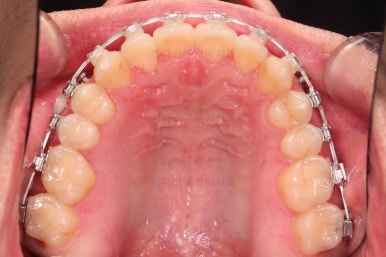

초진 시 입안의 모습입니다.

교합이 많이 안좋습니다.

위아랫니가 서로 엇갈려 가며 지그재그로 껴 들어가야 어금니 맞물림이 생기는데요.

이번 환자분은 아랫니, 아래턱이 전반적으로 앞으로 나와 있어서 교합이 전혀 안되고 있는 상태였습니다.

아무튼 이번 환자분은 위턱 자체가 폭이 좁아서 확장을 먼저 진행했고요.

확장 이 후 유지 기간동안 다른 치열을 가지런하게 해줍니다.